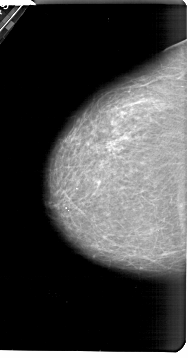

A_1321_1.RIGHT_MLO

RIGHT_MLO LINES 5446 PIXELS_PER_LINE 3376 BITS_PER_PIXEL 12 RESOLUTION 43.5 OVERLAY